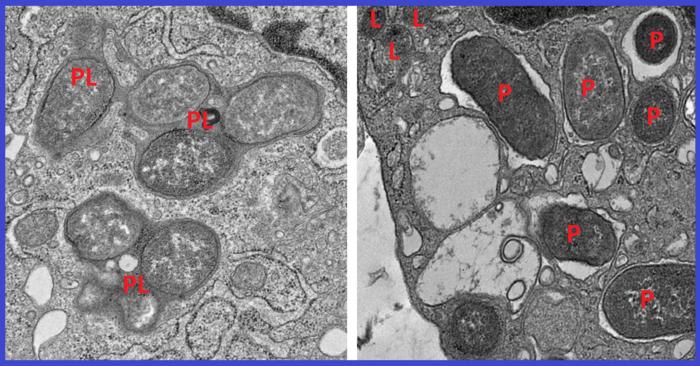

Electron micrographs show how macrophages expressing girdin neutralize pathogens by fusing phagosomes (P) with the cell’s lysosomes (L) to form phagolysosomes (PL), compartments where pathogens and cellular debris are broken down (left). This process is crucial for maintaining cellular homeostasis. In the absence of girdin, this fusion fails, allowing pathogens to evade degradation and escape neutralization (right).